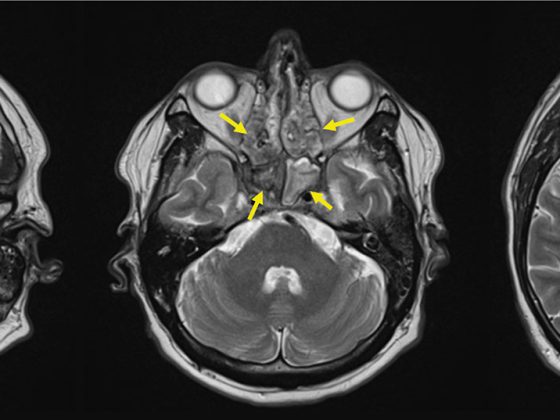

Komplizierte Nierenzysten